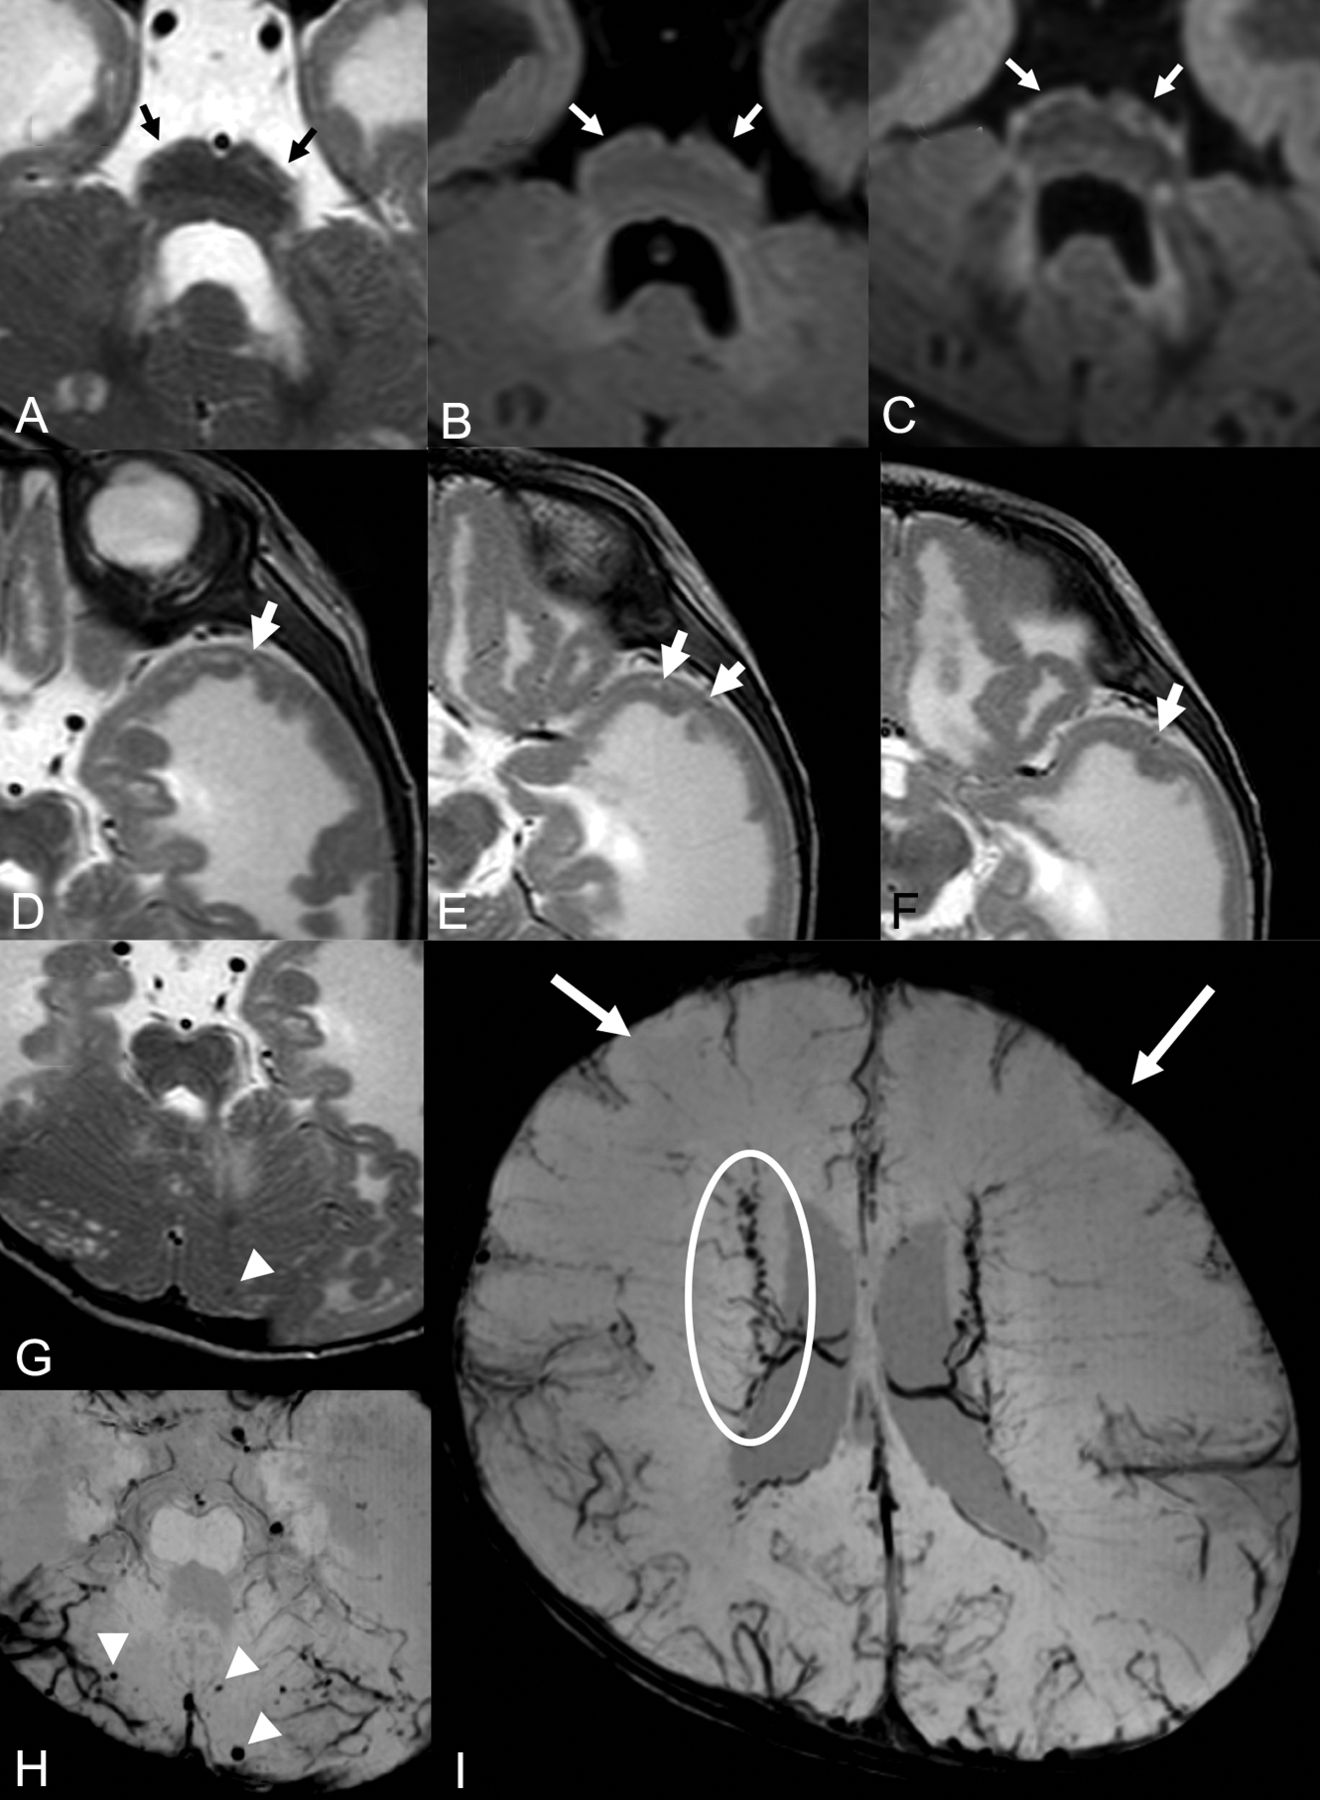

Brain MR imaging of patient 15. Brain stem images on T2WI (A), FLAIR (B), and DIR (C). There is a fluffy structure on T2WI (A, black arrows) and high intensity of the hypoplastic pontine surface on the FLAIR image (B, white arrows). High signal intensity along the brain stem surface on the DIR image is recognized more clearly than on the T2WI or FLAIR image (C, white arrows). T2WIs of the left temporal lobe (D–F) show lissencephalic and the abnormally located cortical superficial vessels running through the superficial layer of the lissencephalic cortex (white arrows). Microhemorrhages were seen in the cerebellar cyst on T2WI (G) and SWI (H). More microhemorrhages are recognizable on the SWI than on T2WI (white arrowheads). Cerebral SWI (I) shows hypoplasia of a superficial cerebral vein in both frontal lobes (white arrows) and dilated and tortuous subependymal veins (white circle).

The clinical and MR imaging findings for all 27 patients are summarized in the On-line Table. All patients showed brain stem hypoplasia (Figs 1 and 2). We observed a fluffy brain stem surface and mild high signal intensity along the surface of a hypoplastic pons on T2WI in 26 patients (96.3%) and FLAIR images in 25 patients (92.6%) (Figs 1A, -B and 2A, -B). The DIR images of all 6 patients showed high signal intensity along the brain stem surface (Fig 1C), and the high signal intensity was recognized more clearly on the DIR images than on the T2WI and FLAIR images.

Abnormally located superficial vessels beneath the cortex were observed in 3 patients (11.1%). The vessels ran through, inside, or beneath the lissencephalic cortex, and they were recognizable especially in the temporal lobes (Figs 1D–F and 2C–E). Hypoplasia of superficial cerebral veins around the frontal lobes was noted in all 5 patients who had SWI findings (Figs 1I and 3C, -D). Dilated and tortuous subependymal veins were identified in 2 of these 5 patients (40.0%) on SWI (Figs 1I and 3C, -D).

Hemorrhages were detected on T2WI in 3 of the 27 patients (11.1%) and on SWI in 3 of the 5 patients (60.0%). Patient 7 showed microhemorrhages in the cerebral and cerebellar cysts on SWI. Numerous microhemorrhages were seen in the cerebellar cysts in patient 15 on T2WI and SWI (Fig 1G, -H). Patient 23 exhibited a hemorrhage in the white matter around the occipital horn of the left lateral ventricle on T2WI and SWI. Patient 25 showed a hemorrhage in the white matter of the frontal lobe on T2WI (Fig 4).

Cerebral MRIs of patient 25. There are hemorrhages in the deep and subcortical white matter of the atrophic left frontal lobe (white arrows) on T2WIs. The location of the hemorrhage in this patient is different from that of the subependymal hemorrhage in a premature neonate.